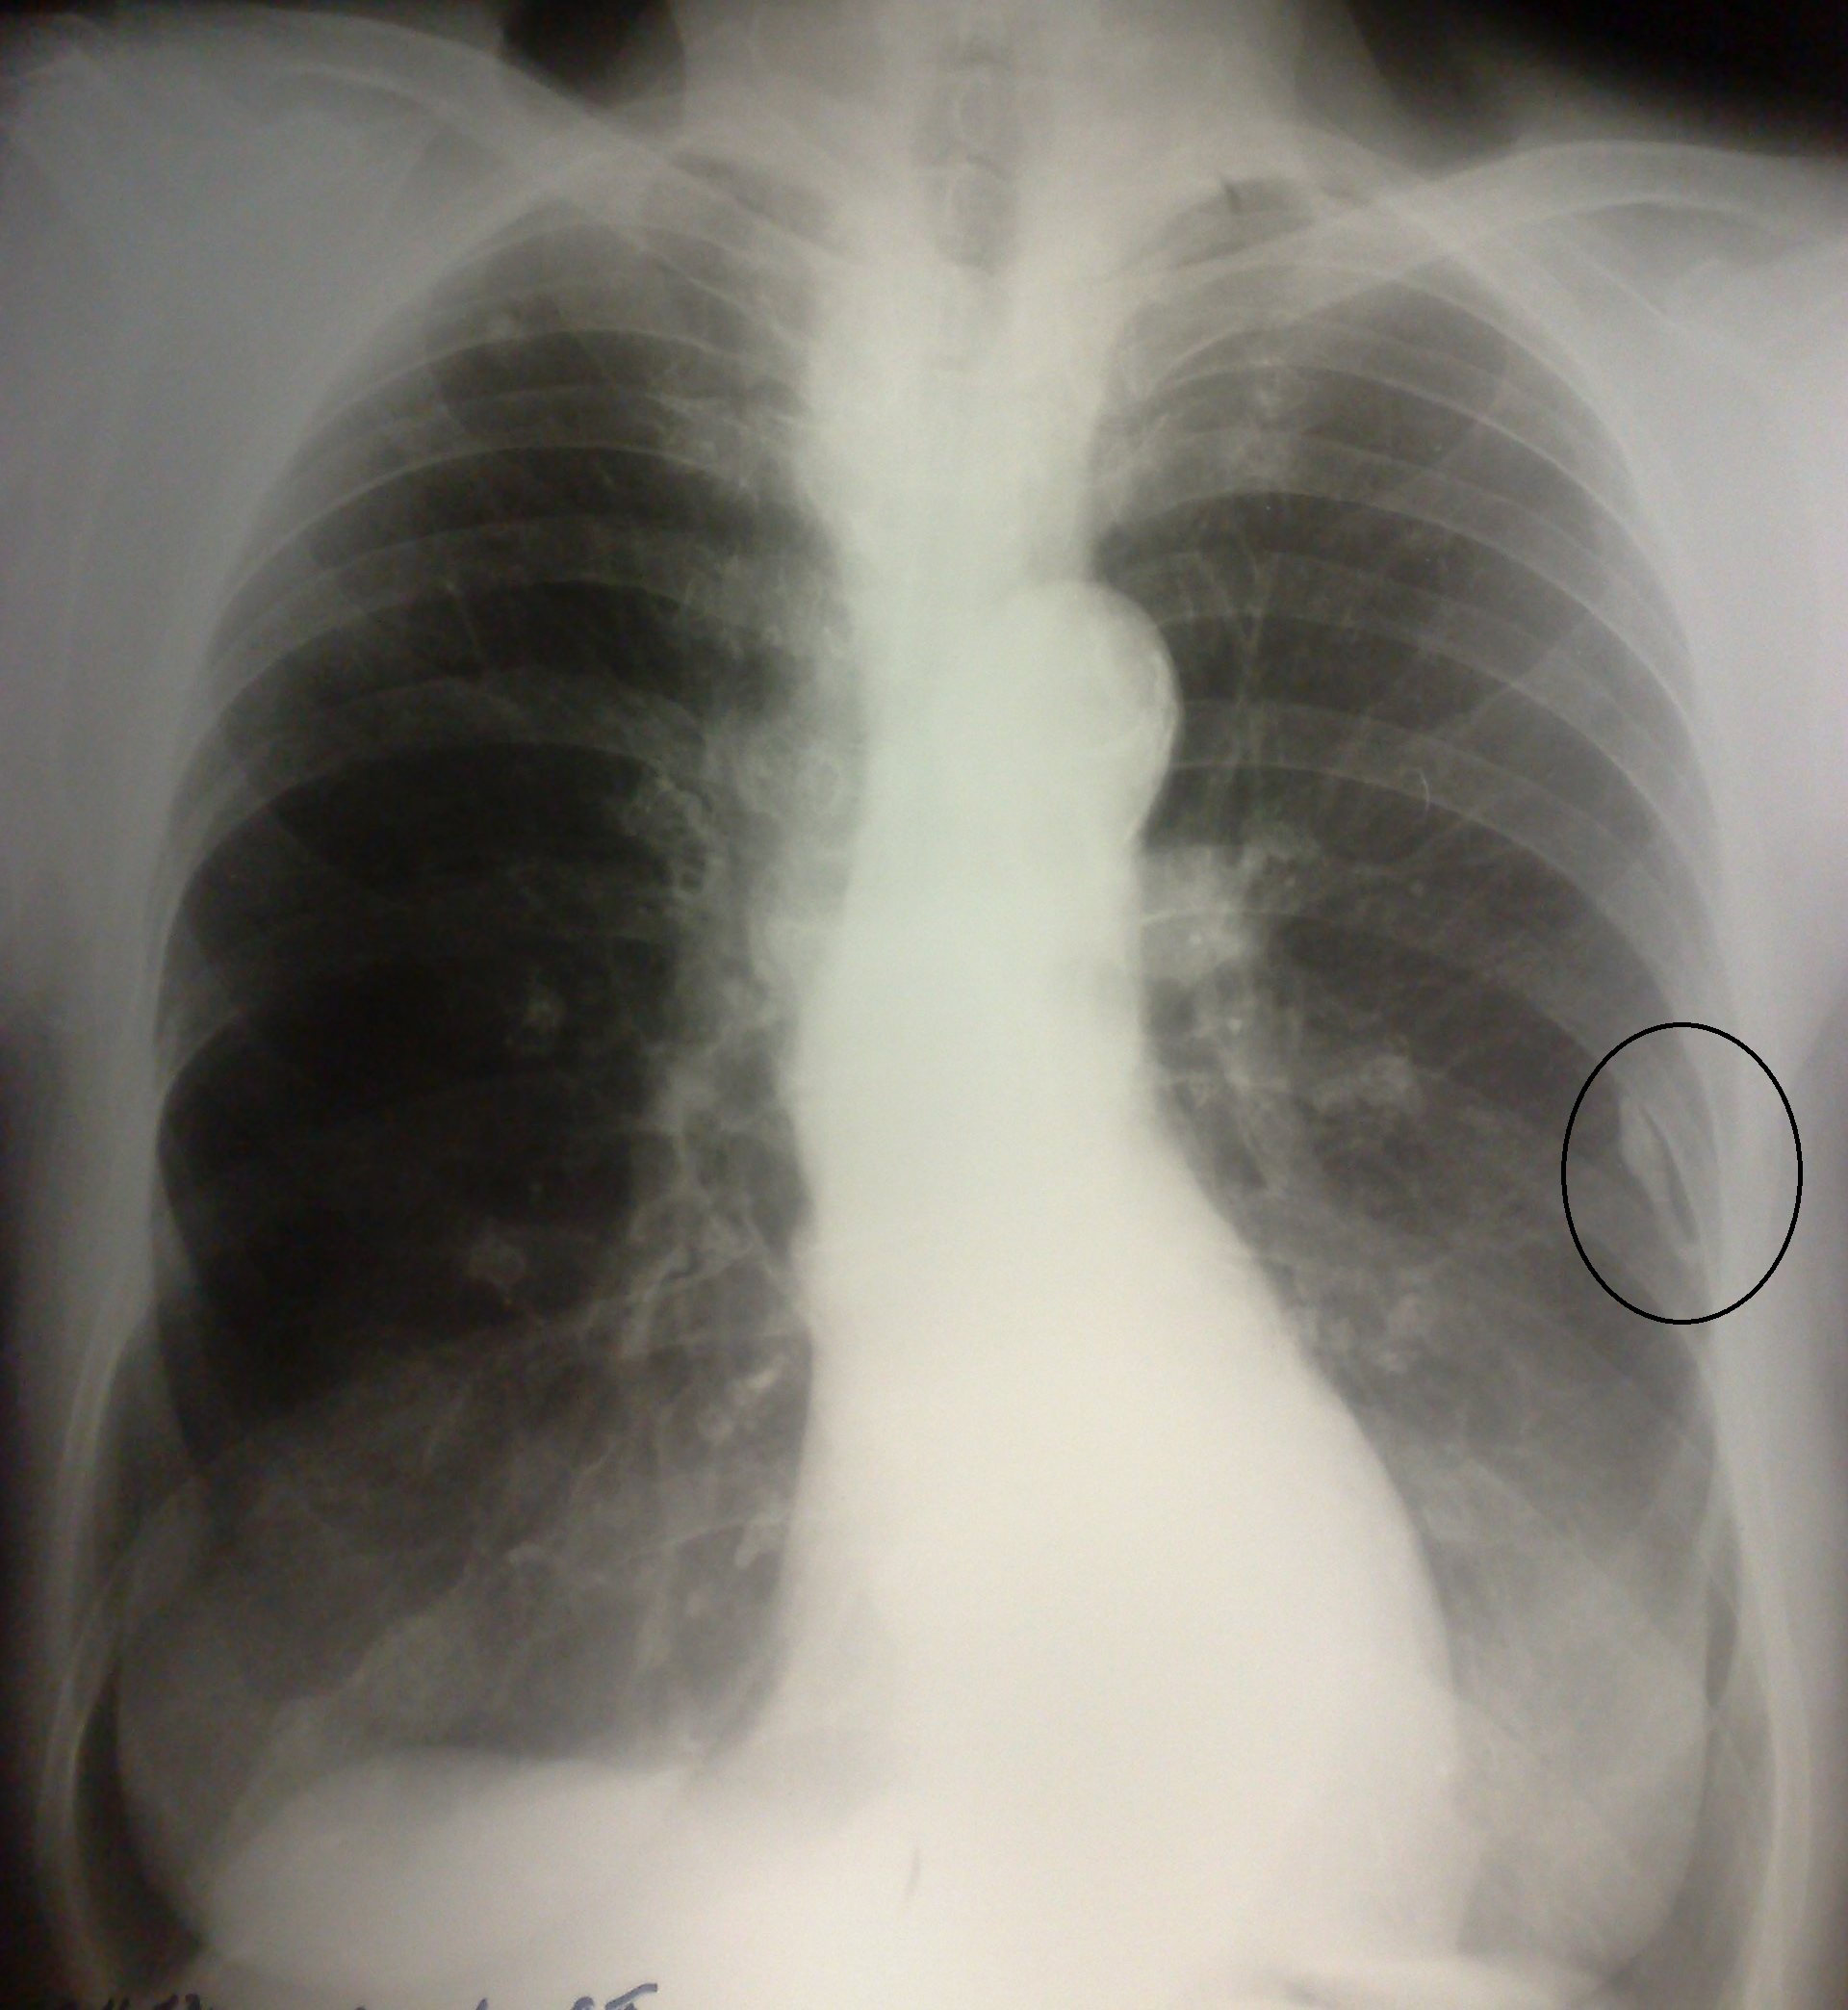

По всей видимости, тут будет, как ранее высказывался коллега, солидный "метатуберкулёзный архив" - там и петрификаты в бронхопульмональных с обеих сторон, и очаги справа (если не свежие, может, туберкуломы) - не менее трёх...

Если Вы про очаги, которые, возможно, не так стары. Вот они - поставил несколько - на Ваш выбор.) Согласен, один может быть бугорком ребра, второй - ортогональным сосудом, третий - иллюзией, другой - обызвествляющимся ребром... Всё может быть. Но качество оставляет место для воображения. Эх, тут бы глаз Mitkampfera, особенно когда издалека, фантазию мне алкса - тогда бы закрутилась свистопляска!)) А так - только предположение. То что хрящи с обеих сторон - это понятно. Но там не только есть они. Когда свой взгляд на снимке малевал, обратил внимание на плотность верхнего средостения у старичка. И диаметр трахеи... очень как-то не совсем. Теперь имею предложение на КТ на зависть всем...

Плевральное наслоение слева+очаг справа на верхушке.

Сдается мне, что необходим правый бок, т.к. верхняя доля справа эмфизематозна, соответственно возможен ателектах н\ доли?